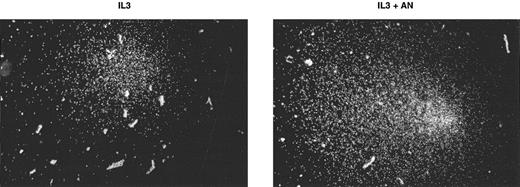

Anandamide enhances colony growth of normal bone marrow progenitors induced with IL-3.Normal mouse bone marrow colony cultures were performed to investigate whether anandamide enhances IL-3–stimulated colony growth. In two independent experiments, a twofold elevation of colony formation was observed when the cells were cultured with IL-3 plus anandamide as compared with IL-3 alone (Table 2). Anandamide not only increased colony numbers, but also showed an effect on the size of the colonies (Fig 5). More colonies containing 250 cells or more were found in cultures with IL-3 plus anandamide. Mega-size colonies of 1,000 cells or more were found in IL-3 plus anandamide cultures, but none in colony cultures with IL-3 alone.

Effect of ananadamide on the size of IL-3–induced normal bone marrow colonies. Examples of representative IL-3–induced normal bone marrow colonies after 14 days of culture with (IL-3+AN) or without anandamide (IL-3).

The results presented in Table 2 and Fig 5 show that the synergism between IL-3 and anandamide is also evident in normal bone marrow colony formation. A greater number of IL-3–dependent colonies were formed in the presence of anandamide. These results indicate that, in the presence of anandamide, IL-3 stimulates the outgrowth of additional populations of precursor cells. IL-3 plus anandamide also stimulated colonies of greater size, which would indicate that the combination of the two factors augments the production of progeny from individual precursor cells as well. Whether anandamide synergizes with other HGFs in the stimulation of normal marrow precursor cells is currently under investigation.